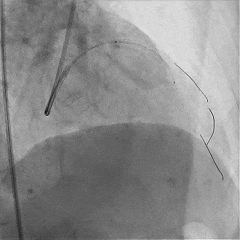

处理RCA病变:

Runthrough导丝至RCA远端,预扩球囊扩张RCA近中段病变处

植入支架Tivoli 2.75*18mm一枚

高压球囊后扩张后,无残余狭窄,血流TIMI3级

双侧造影,观察闭塞起始位置、长度、走行等